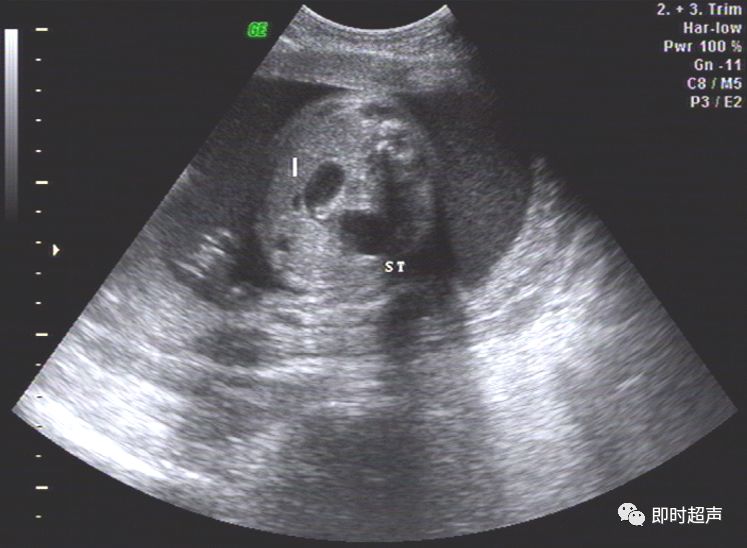

胎儿胃泡可见隔光带

(r-右侧,l-左侧,u-十二指肠,st-胃泡,sp-脊柱)

图三:胃泡正常